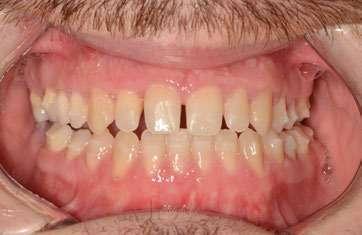

1. Análisis extraoral (Ilustración 1):

 Biotipo facial dolicofacial compatible con Clase III.

 Sonrisa gingival superior.

 Asimetría mandibular con desviación del mentón hacia la izquierda.

1 Ilustración 1. Fotografías extraorales iniciales de estudio.